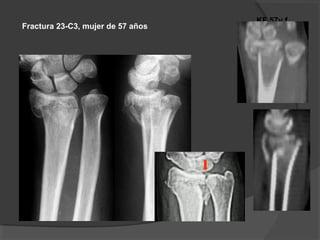

Fractura 23-C3, mujer de 57 años

8 m

Dorsal approach

- Visualización directa

- Mayor irritación de los tendones extensores

- Riesgo de rotura secundaria de los tendones